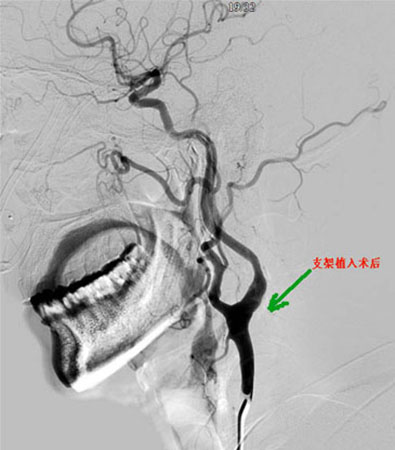

1月12日,家住红塔区春和街道的孔大爷,高高兴兴地从医院办理了出院手续,准备回家。现在的他感觉神清气爽,又恢复了健康,而这一切得益于神经外科开展的一项新技术——颈动脉支架手术。 今年66岁的孔大爷因高血压,不时伴有头晕、脑梗等病症,来医院心内科看病时检查出左侧颈动脉狭窄,于是住进了我院神经外科。1月4日,王和平医生为他做了颈动脉支架手术,这也是我院第一例在未请外来专家的情况下独立开展的颈动脉支架手术。经过几天的治疗和休养,孔大爷恢复了健康。 颈动脉狭窄,是指作为血液由心脏通向脑和头其他部位的主要血管的颈动脉出现狭窄的症状。颈动脉狭窄多是由于颈动脉的粥样斑块导致的颈动脉管腔的狭窄,其发病率较高,在60岁以上人群中患颈动脉狭窄者约占9%,多发生于颈总动脉分叉和颈内动脉起始段。有些狭窄性病变甚至可能逐渐发展至完全闭塞性病变。颈动脉狭窄可以通过药物控制或外科手术治疗。 临床上依据颈动脉狭窄是否产生脑缺血症状,有症状性颈动脉狭窄和无症状性颈动脉狭窄。 诊断标准一般为年龄大于60岁以上的男性,有长期吸烟史,肥胖,高血压、糖尿病及高血脂等多种心脑血管疾病的危险因素人群,或体检时发现颈动脉血管杂音,需要进行进一步检查,并通过无创性辅助检查的结果综合分析多可作出诊断。 检查方法主要有多普勒—超声检查、磁共振血管造影(MRA)、CT血管造影(CTA)及数字减影血管造影。其中数字减影血管造影是诊断颈动脉狭窄的“金标准”,可以详细地了解病变的部位、范围和程度以及侧支形成情况;帮助确定病变的性质如溃疡、钙化病变和血栓形成等;了解并存血管病变如动脉瘤、血管畸形等,动脉造影能为手术和介入治疗提供最有价值的影像学依据。目前神经外科已成功开展此项检查200余例,无一例出现意外。 目前颈动脉狭窄的治疗目的在于改善脑供血,纠正或缓解脑缺血的症状;预防TIA和缺血性卒中的发生。依据颈动脉狭窄的程度和患者的症状进行治疗,包括内科治疗、外科治疗。主要有以下几种:内科治疗,内科保守治疗的目的是减轻脑缺血的症状,降低脑卒中的危险,很好地控制现患的疾病,如高血压、糖尿病、高血脂症及冠心病等;外科手术治疗,颈动脉狭窄外科治疗目的是预防脑卒中的发生,其次是预防和减缓TIA的发作。标准的手术方式为颈动脉内膜切除术(CEA)和介入治疗(颈动脉支架成形植入术CAS)。神经外科均已能独立、熟练的开展。 颈动脉支架植入术相对CEA有下列优势:①不需全麻,部分有严重并发症的患者亦可耐受;②病变可不局限于颅外段颈动脉;③创伤小,手术时间短;④可同时对颈动脉、椎动脉、冠状动脉进行治疗。(王和平) |